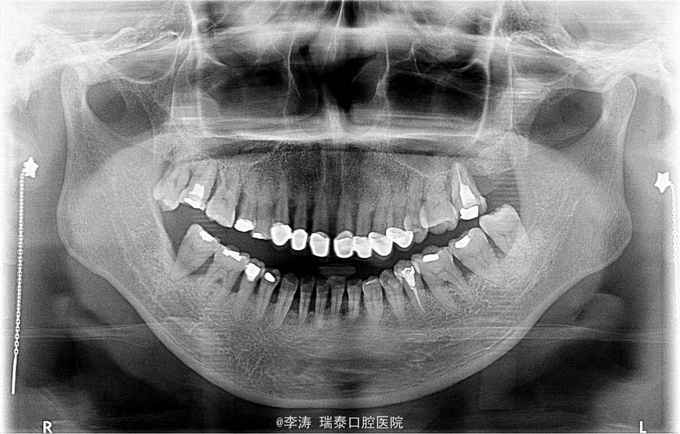

13到24烤瓷冠修复,牙根暴露约3mm,黑三角明显,中位笑线,前牙松动不明显。 X线片11,12,13均吸收至根尖三分之一,21,22,23,24约根中三分之一,根尖未见明显暗影

患者因不考虑拔除后种植治疗方案,遂制作美学蜡形,患者接受,行上前牙根管治疗后11,12,13及21,22,23,24分别联冠修复 先行牙周基础治疗 牙周稳定后行13,12,11,21,22,23根管治疗。 接下来纤维桩,全冠修复